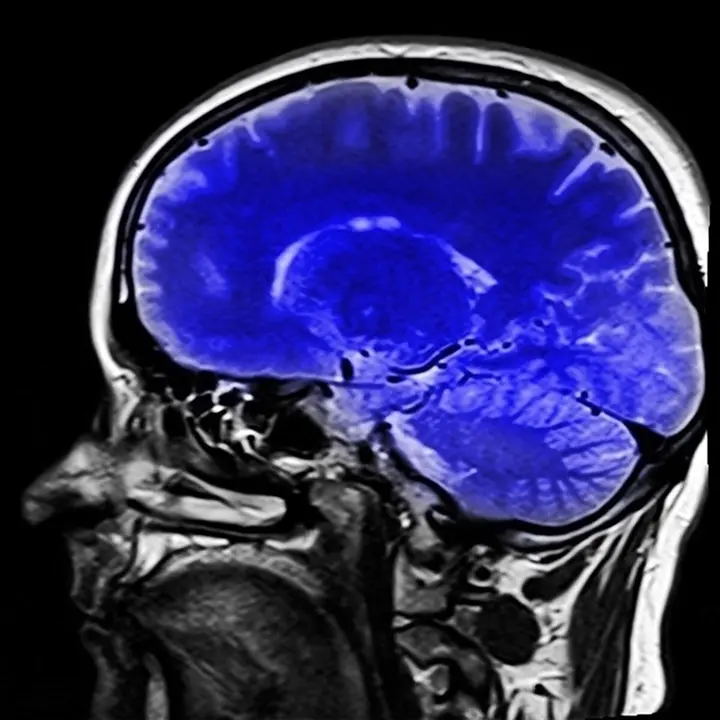

El Hospital Universitario Marqués de Valdecilla y el Instituto de Investigación Sanitaria Valdecilla (IDIVAL), organismo dependiente de la Consejería de Sanidad, han participado en un estudio internacional que ha concluido que la presencia de la proteína amiloide beta en el cerebro se asocia a una peor memoria en personas sin demencia.

El doctor Pascual Sánchez-Juan ha explicado que hoy en día se puede determinar si una persona presenta esta proteína en el cerebro "bien mediante técnicas de medicina nuclear como el PET cerebral o estudiando los niveles de amiloide beta en el líquido cefalorraquídeo extraído mediante punción lumbar".

Ha destacado que el depósito de la proteína amiloide beta en el cerebro es una característica esencial de la enfermedad de Alzheimer y que su aparición se produce décadas antes del inicio de la patología. En este sentido ha calificado como "esencial" lograr un mejor conocimiento de los estadios iniciales del Alzheimer para detectar lo antes posible a las personas en riesgo de desarrollar esta enfermedad.